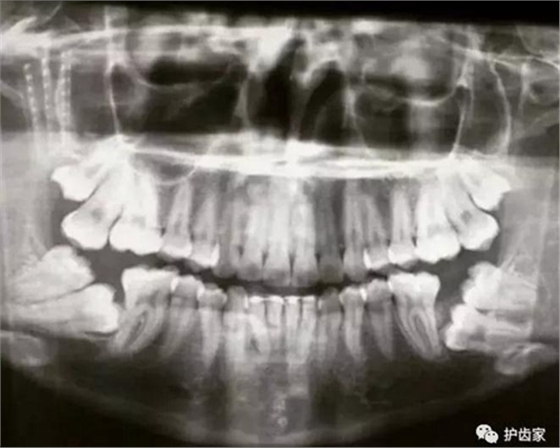

拍片的必要性

拍片是為了了解智齒周圍情況,也是為了了解智齒結構,牙根結構千變萬化,有可能是融合成一個根,也可能是八爪根。不同牙根不同位置及方向,只有通過拍片來確認。

通過拍片可以了解牙齒本身:生長方向,牙根數目,牙根是否彎曲,膨大等。

與重要解剖結構的位置關系:如上頜磨牙與上頜竇的關系;下頜磨牙與下頜神經管的關系;兒童在混合牙列期恒牙與乳牙胚的關系等??梢詼p少拔牙的風險。

預知其他病變:如頜骨內有無埋伏牙,多生牙,囊腫等。